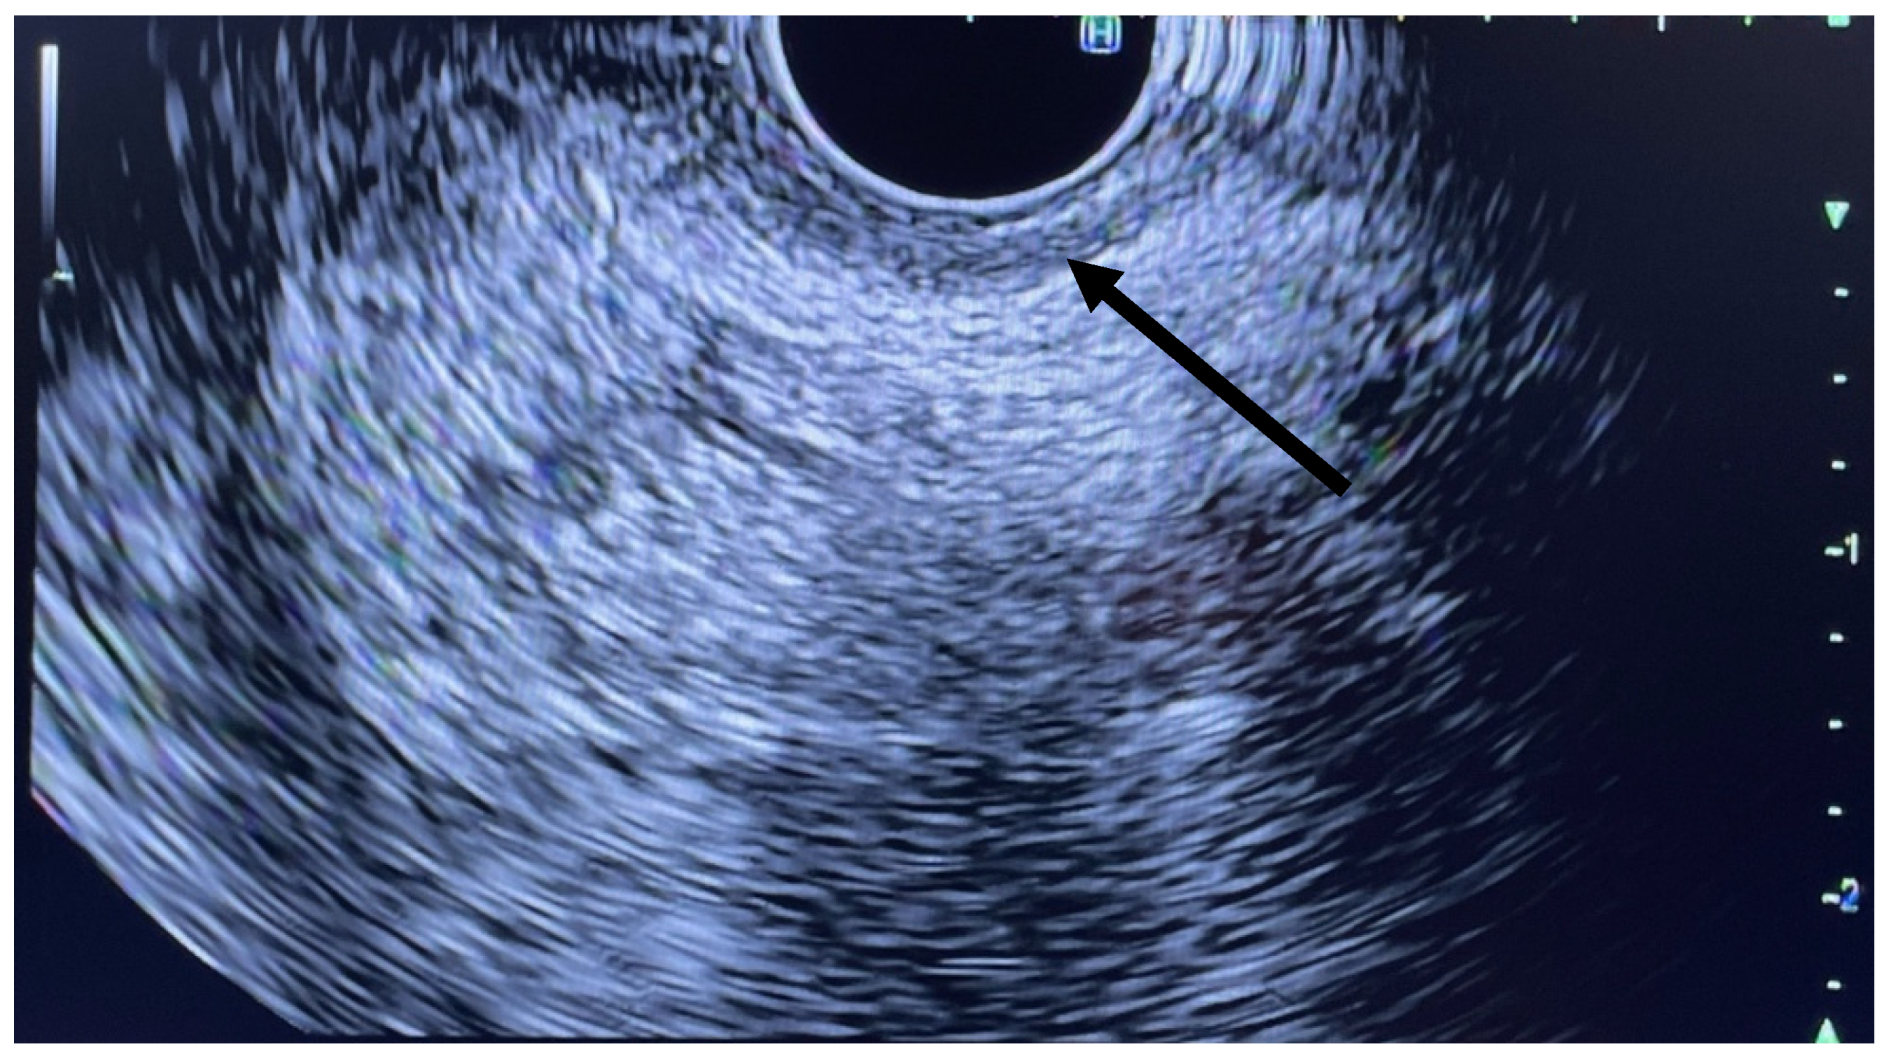

EUS was performed using a linear array echoendoscope (Figure 1, Figure 2 and Figure 3). Eighty units of type A botulinum neurotoxin was diluted in 2 cc of isotonic saline. An echoendoscope was introduced into the anal canal. The internal sphincter was identified sonographically and a 25-gauge needle was introduced into the internal sphincter. Then, 0.5 cc of saline-containing 20IU BTX was injected into the internal sphincter. The needle was withdrawn, the scope was rotated 90 degrees and the second injection was given. This process was repeated for a total of 4 times giving 0.5 cc per quadrant. Conscious sedation or MAC anesthesia was used for the procedure.

Figure 2. Linear EUS with arrow pointing to IAS.